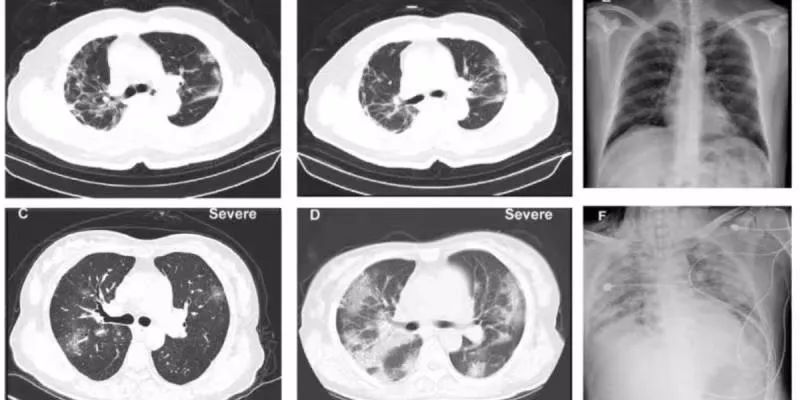

新冠肺炎患者的CT影像图 , 肺部出现毛玻璃样

病理搞不清楚 , 治疗就会盲目 深一度:在新冠肺炎的诊疗中 , 病理检查的现状怎样? 刘良:病理上没有完整的、系统的东西 , 可能有个别人做了穿刺或者活检 , 但都是很局限的 , 它不能代表整体 , 基本上是空白 。 现在死亡人数过千 , (这种缺失)按理说是不应该的 。 深一度:病理学检查为何重要? 刘良:打个比方 , CT检查就像卫星 , 如果地球上发生了一场战争 , 卫星只能看个大概 。 最核心的是要有人到前沿阵地去 , 看见敌人死了多少 , 我们的防御出了什么问题?敌人用什么武器 , 我们武器是什么样子?像侦察兵一样 , 指导后方打仗 。 病理研究就干这事儿 。 CT显示 , (新冠肺炎患者)肺上出现毛玻璃样 。 我们要搞清楚是什么导致肺出现毛玻璃样 , 是水肿?出血?感染?纤维化?里面起反应的是中性白细胞、单核细胞还是淋巴细胞?搞不清楚的话 , 治疗上就会盲目 , 一片乱杀 。 病理研究也关注传染途径的问题 。 比如粪口传染 , 肠道里的病毒到底分布在什么地方?口腔、食道、胃、十二指肠还是结肠?不同情况的病人治疗也完全不一样 。 以后 , 如果要对新冠肺炎做实验 , 设计研究模型 , 也需要病理研究的结果 。 深一度:如果可以 , 新冠肺炎的病理研究可以做到什么程度? 刘良:我们需要对新冠肺炎的死者遗体进行解剖 , 取样 , 然后做切片 , 可以研究病毒在人体的分布状态 , 以及身体哪个部位对病毒有反应 。 具体到病毒对哪个组织、哪个器官 , 器官的哪个局部、哪些细胞损害更多 。 病毒攻击的方向、靶点在哪里 , 我们就要对这个靶点做研究 , 做一些干预、防御 。 (这个缺失)对抢救治疗有延误 , 对将来的研究也有影响 , 所以很着急 。 深一度:病理研究能为新冠肺炎的治疗提供什么支持? 刘良:肯定能提供支持 。 以往 , 有很多临床不清楚的问题 , 都能在病理医生的解剖结果中找到答案 , 像判官一样 。 新冠病毒很奇怪 , 远离气管 , 在肺的周围比较多 。 所以取咽拭子的时候 , 病人要深深的把肺周围的病毒咳出来 。 为什么是这样的?目前还不知道 。 我们需要在显微镜下去验证 , 肺的哪个部位病变更明显 , 是靠近中间 , 还是外围?具体是什么样的病变 , 哪一块的炎性细胞比较多? 有了这些病理研究 , 就会去思考 , “为什么病毒会到这个地方去?”假设病毒在肺的外围多 , 那么它可能不是从呼吸道传入的 , 而是从消化道进入 , 跟着血液循环到边缘的毛细血管 , 然后繁殖 , 从外向内对肺部进行攻击 。 如果是这样 , 可能需要处理的就是血液上的问题 , 而不仅是针对肺的雾化 , 治疗的重点和方向就不一样了 。 另外 , 这个病毒对不同的人作用不一样 , 病例积累得越多 , 对临床治疗越有用 。 如果有病理解剖的知识 , 会更方便 。